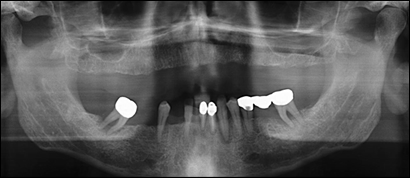

Fig 1: A 55 year old male presented requesting dental implants. His upper arch was completely edentulous. His lower teeth were diseased.

Fig 10: A radiographic view of the dental implants prior to the placement of the porcelain bridges.